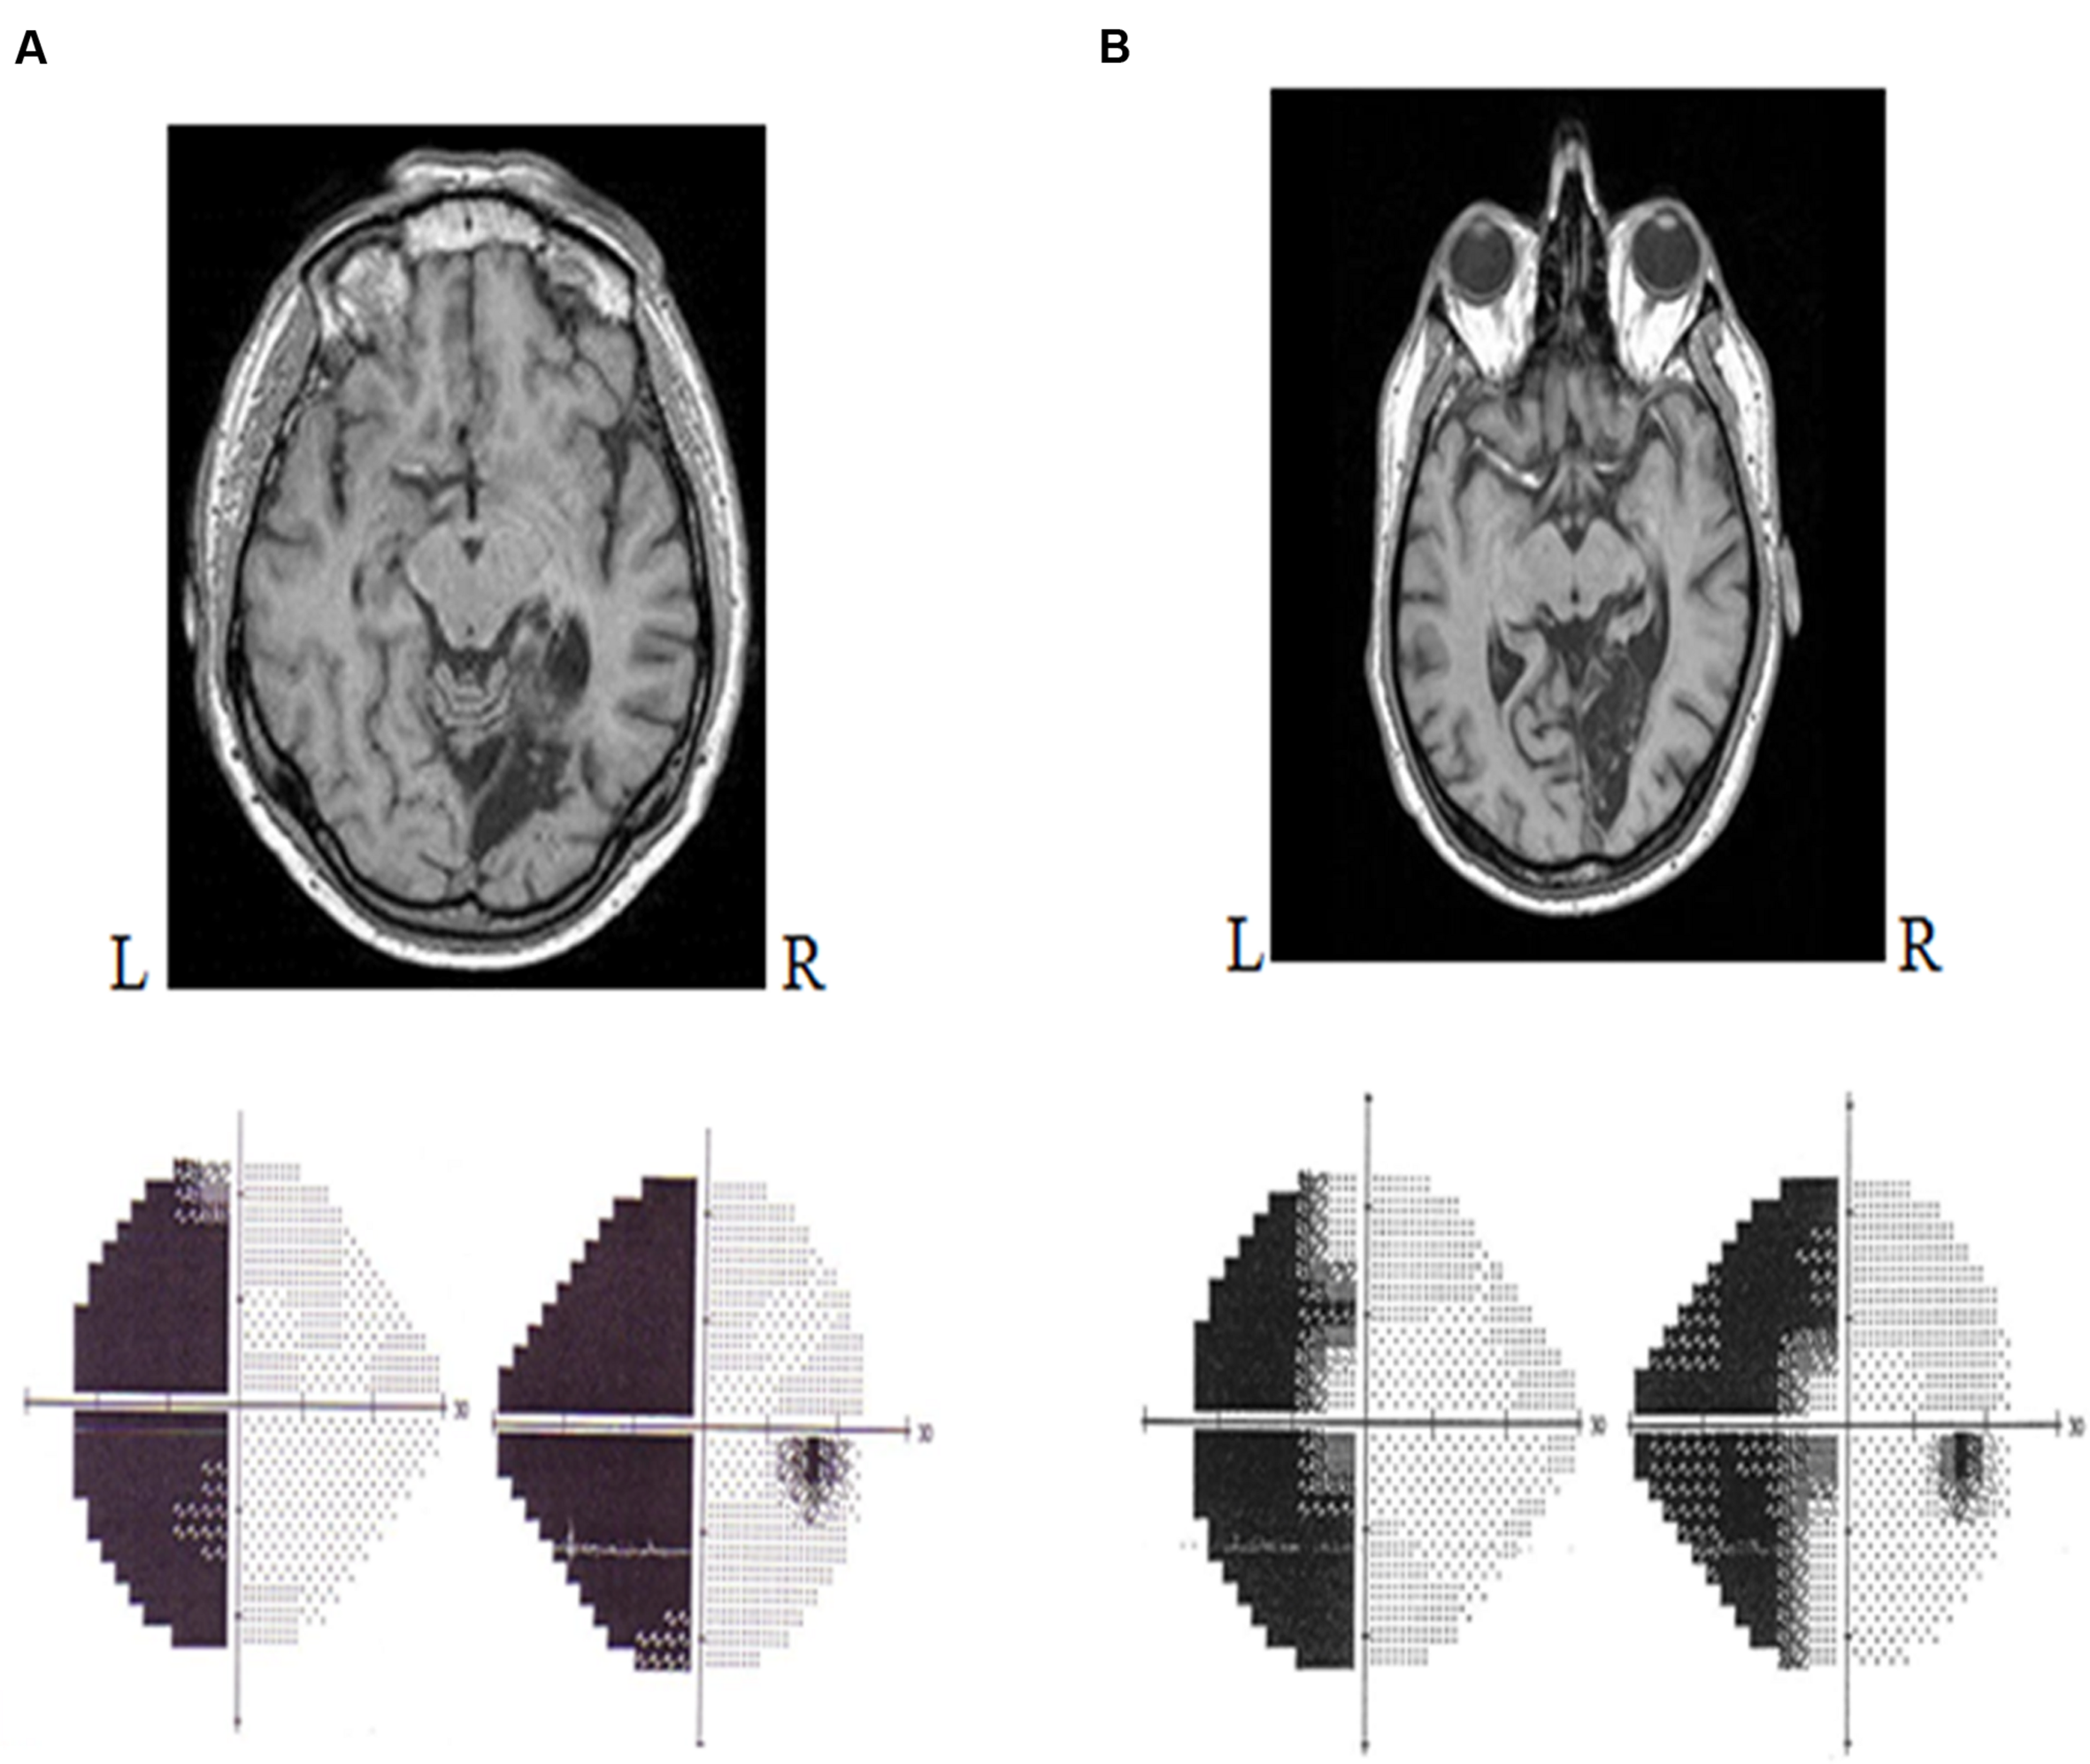

Lesions that occur between the optic chiasm and the primary visual cortex (V1) can provoke a type of visual deficit known as a cortical visual impairment. Such deficits translate to visual field defects or to more complicated visual defects, depending on the location of the lesion. Clinically, the most common visual field defect to follow a retrochiasmatic lesion is homonymous hemianopia (HH) (Zihl, 2011). In fact, HH occurs in 30% of patients that have suffered a stroke (Zhang et al., 2006a). Lesions in the primary visual cortex (V1) lead to loss of conscious access to most visual information in the contralesional visual field (Holmes, 1918; Weiskrantz et al., 1974). HH is typically defined as a visual field defect in which vision in the contralesional half of the visual field has been eliminated but no ocular damage has occurred (Holmes, 1918). It is considered to be both lateral and homonymous because it alters the same visual field expanse for both eyes. Specifically, it affects the information projected onto both the temporal hemiretina of the contralesional eye and the nasal hemiretina of the ipsilesional eye. Accordingly, a patient with a right occipital lesion will present with left HH (Figure 1), whereas a patient with a left occipital lesion will exhibit right HH.

FIGURE 1

Humphrey automated perimetry (SITA FAST 24/2). (A) Left homonymous hemianopia without macular sparing. (B) Left homonymous hemianopia with macular sparing.

In most cases, the hemianopic defect is congruent: the losses to the contralesional field of each eye are symmetric to the point that they can be superimposed (Zihl, 2011). A hemianopia that affects the vertical meridian (i.e., the entire lateral visual field) is known as a hemianopia without macular sparing. Contrariwise, an incomplete hemianopia, whereby the lateral visual field is partially preserved because the central portion (macula) is conserved, is known as a hemianopia with macular sparing (Zihl, 2011; Figure 1B). Macular sparing is observed when the vascular territory of the occipital pole is preserved, the spared zones of the visual field corresponding to the preserved cortical regions (Zhang et al., 2006b). In addition, some authors have proposed that macular sparing stems from the bi-hemispheric cortical representation of the central field (Brysbaert, 2004).